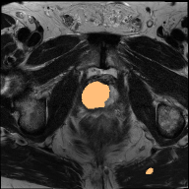

4.3 Qualitative Results of DSPIF

Some qualitative results of the proposed DSPIF are shown in Fig. 3. Both USPIF and LSPIF generate images with diverse appearances while preserving the same topological structure as the original image. Inheriting from the property of connected filters, the proposed DSPIF does not create any new contours. It is also noteworthy that monotonically increasing contrast change map pixels with the same graylevel to the same output graylevel. Differently, the output of DSPIF does not only depend on the input graylevel, but also the image structure. As shown in the first row of Fig. 3, for similar input graylevels on different pixels, USPIF may output very different graylevels on these pixels. Yet, the topological image structure is preserved.

Some qualitative segmentation results on the three datasets are shown in Fig. 4, where we can observe that the proposed DSPIF achieves accurate segmentation results.